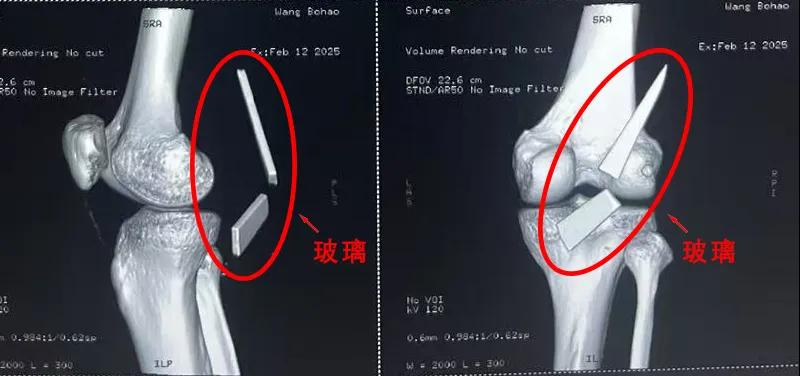

13厘米碎玻璃扎入腿中,漯河醫(yī)專二附院顯微外科緊急“拆彈”......

“兩塊碎玻璃加起來(lái)有13cm長(zhǎng),這要是傷到了血管,后果可是不敢設(shè)想......”雖然手術(shù)已經(jīng)順利結(jié)束,回憶起當(dāng)時(shí)的畫面,患者家屬還是心有余悸。

患者家屬這才開(kāi)始意識(shí)到問(wèn)題的嚴(yán)重性,便帶著孩子到鄉(xiāng)鎮(zhèn)衛(wèi)生院檢查——結(jié)果顯示右膝關(guān)節(jié)后方竟然殘留著兩塊兒鋒利的碎玻璃,測(cè)量后預(yù)估玻璃總長(zhǎng)將近13厘米!

由于玻璃位置毗鄰坐骨神經(jīng)和股動(dòng)脈,一旦刺破股動(dòng)脈,將嚴(yán)重威脅生命。家屬著急萬(wàn)分,想著能否盡快手術(shù)取出碎片,于是慕名來(lái)到漯河醫(yī)專二附院(漯河市骨科醫(yī)院、漯河市立醫(yī)院)手顯微外科(修復(fù)重建骨感染科)。

術(shù)中,馬廣輝醫(yī)生憑借扎實(shí)的理論知識(shí)和嫻熟的顯微外科技術(shù),順利找到深深刺進(jìn)肌肉的兩塊玻璃,肉眼可見(jiàn)玻璃尖端距股動(dòng)脈僅有不到半公分的距離!如果患者再耽誤半天或者再多活動(dòng)幾次膝關(guān)節(jié),小指粗的股動(dòng)脈很有可能被玻璃扎破,后果難以想象。

最終,馬廣輝醫(yī)生在血管、神經(jīng)表面順利取出兩塊玻璃碎片,拆除了埋在患者膝關(guān)節(jié)的“炸彈”。在告知患者家屬術(shù)中情況后,家屬懸著的心終于放了下來(lái)。